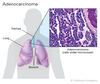

Qual o tipo de carcinoma broncogênico mais comum em não fumantes / mulheres / pacientes < 45 anos?

ADENOCARCINOMA

Qual o tipo de carcinoma broncogênico mais comum no geral?

ADENOCARCINOMA

Quais os tipos de carcinoma broncogênico de localização PERIFÉRICA?

ADENOCARCINOMA e GRANDES CÉLULAS

Um tumor pulmonar que se apresenta com DERRAME PLEURAL é mais provavelmente que tipo?

PERIFÉRICO

(Adenocarcinoma ou Grandes Células)

Uma variante bem diferenciada do adenocarcinoma que cresce ao longo dos alvéolos, sem invadi-los. Melhor porgnóstico.

Pode se manifestar como massa, infiltrad difuso multinodular ou opacidade em vidro fosco na TC